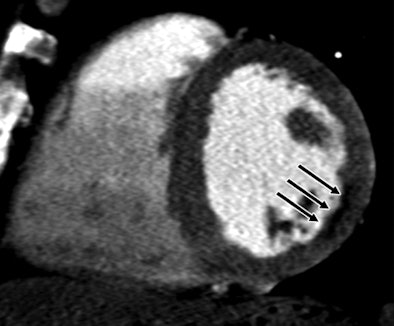

| A 51-year-old man with history of diabetes mellitus presented with typical angina. Above, curved multiplanar reformatted cardiac CT angiographic image read before perfusion shows prominent motion artifact in right coronary artery (arrows) that persisted through all cardiac phases. Below, thick short-axis CT perfusion image at midventricular level shows perfusion defect (arrows) during stress CT perfusion in the inferior and inferolateral segments that is partially reversible during rest CT perfusion. Bottom, reference-standard invasive angiogram findings confirm the presence of severely stenotic lesion in right coronary artery (arrow) that was seen at postperfusion cardiac CTA image reading. Images republished with permission of the Radiological Society of North America. |